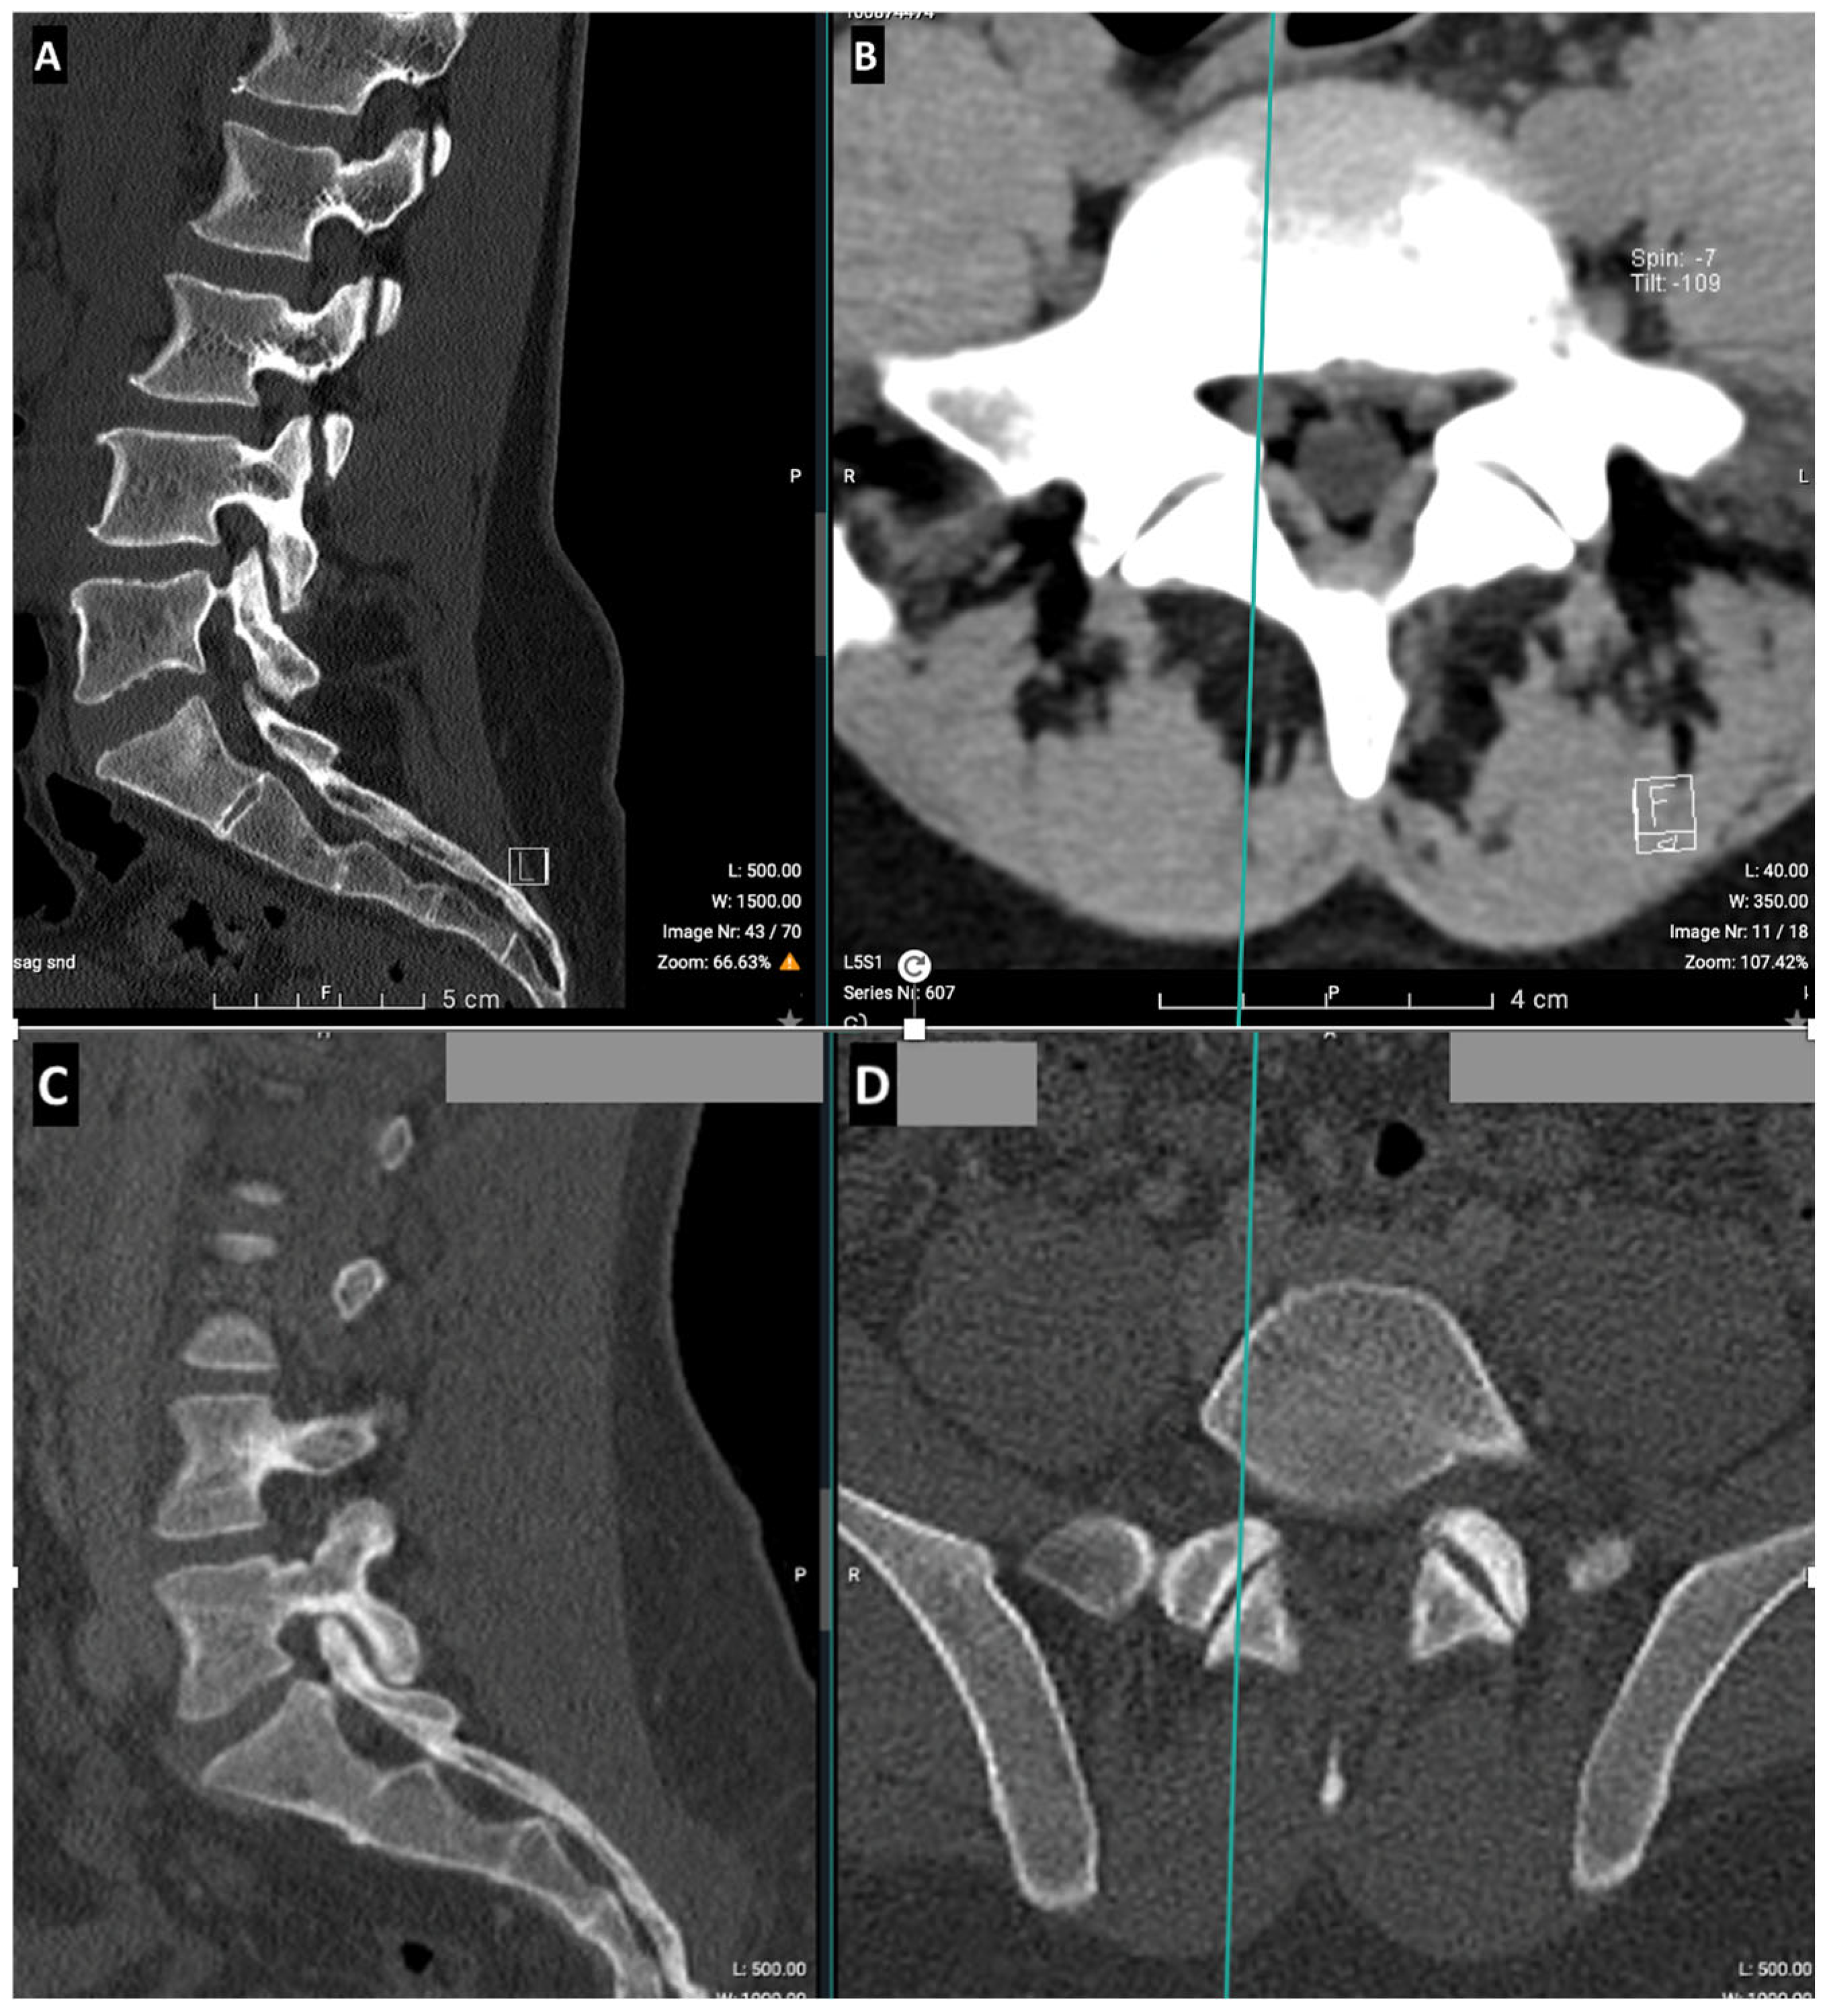

2.2. CT Imaging Research Methodology